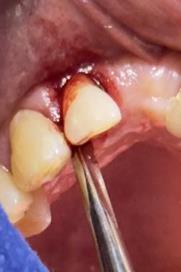

Figura 7. Exodoncia de la unidad dental, revisión del alveolo, curetaje y retiro de exudado purulento con cucharilla de lucas.

Elaboración: Los autores.